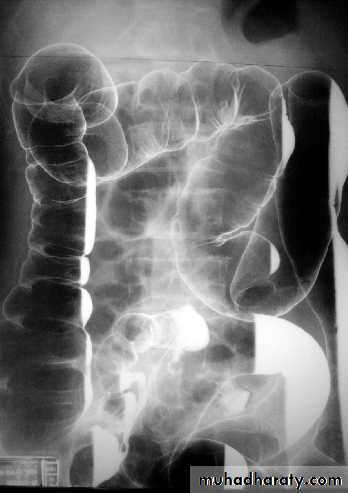

UC

The colon is distended with air

The descending & sigmoid colon are featureless (no haustral pattern)

Thumb printing